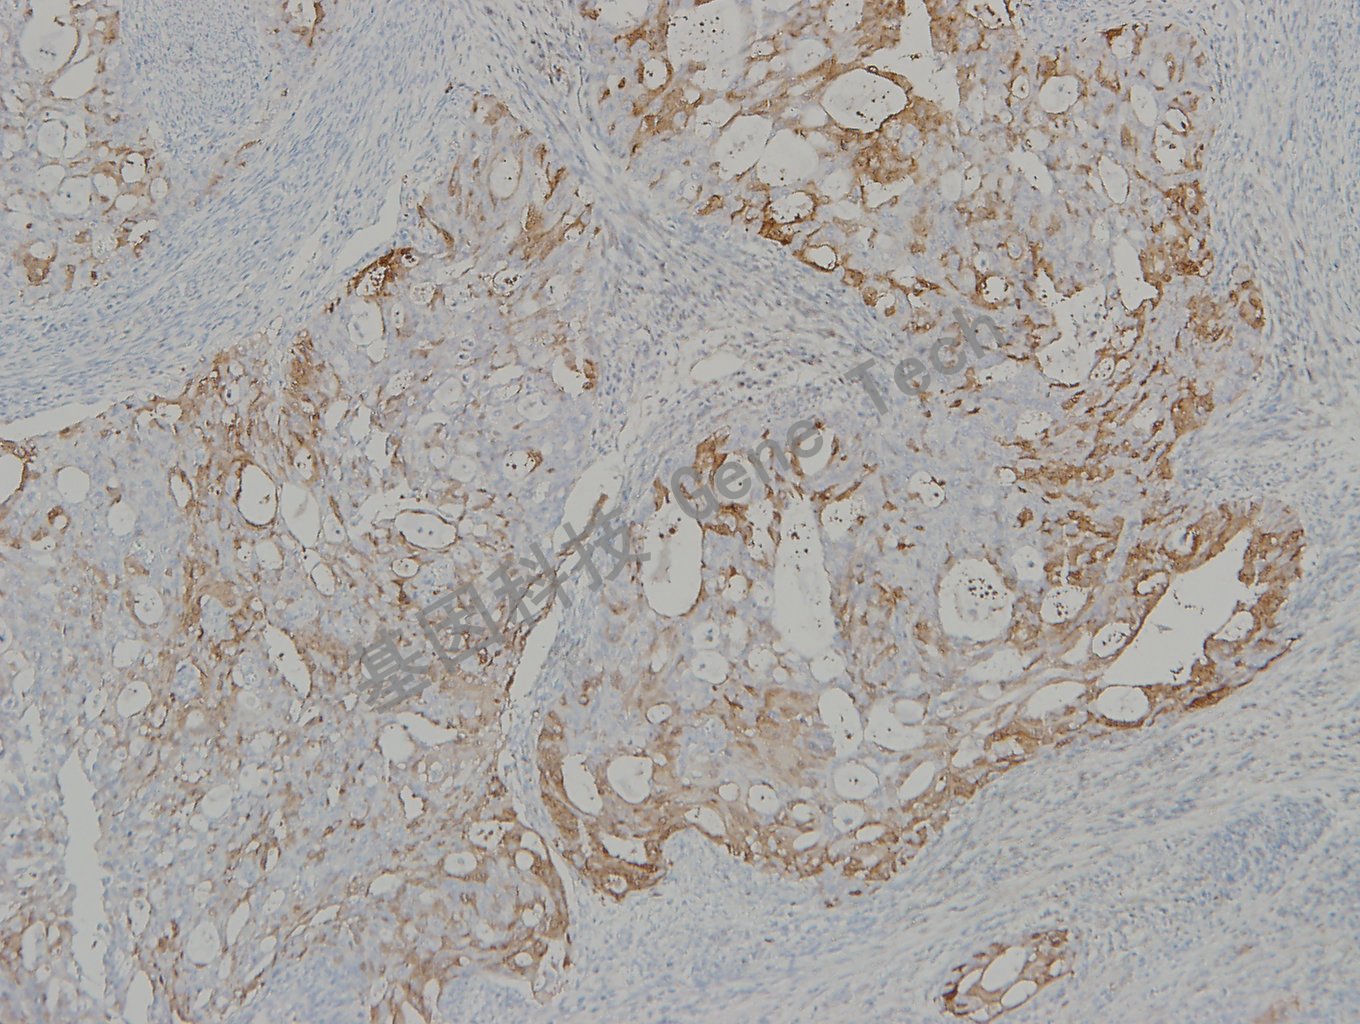

子宫内膜癌石蜡切片,用 p16(GT2330)染色,细胞浆/细胞核阳性,DAB 显色。